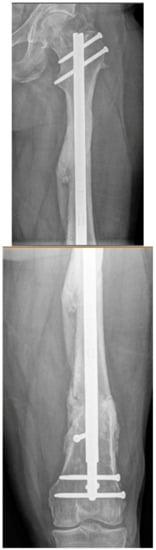

3.3. Case 3-Single-Plane Correction with Nail: Tibia

An adult male with no comorbidities presented with varus malunion following intramedullary tibial nailing, reporting symptomatic medial knee pain (Figure 8A). The CORA analysis revealed a varus deformity of 12 degrees. With a deformity in the coronal plane, surgical access was through an anterior approach using a focal dome osteotomy for correction. The anterior compartment was elevated, and a drill bit was placed in the CORA, with a parallel drill guide used to draw the arc with a second drill bit. The osteotomy was completed with an osteotome. The alignment was maintained during reaming using a temporary plate (Figure 8B). The patient underwent compression nailing using a magnetic motorized nail, allowing for subsequent compression as needed after discharge (Figure 8C). The patient felt pain-free at 12 weeks, yet was encouraged to return for regular follow-up examinations and X-rays until radiographic healing. Patient lost to follow-up after 6 months (Figure 8D).

(A) Adult male with varus malunion deformity after a prior tibia fracture and nailing. (B,C) Patient underwent focal dome osteotomy with compression nailing using a magnetic motorized nail for early and subsequent nail compression. (D) Patient declined to follow-up after 12 weeks, citing absence of pain. Patient returned at 6 months at request of surgeon, still without pain. Magnetic nail recompressed. Patient lost to follow-up after 6 months.